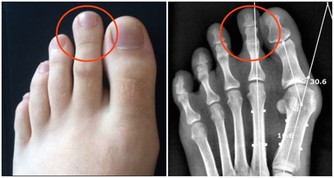

跟癌症、心腦血管疾病相比,關節炎似乎算不上多麼致命的疾患,然而它發作時的痛苦程度,讓所有患者一想起來就心有餘悸。想想手部、手腕、腳部關節疼痛、腫脹、僵硬的滋味吧,你一定不會喜歡的。